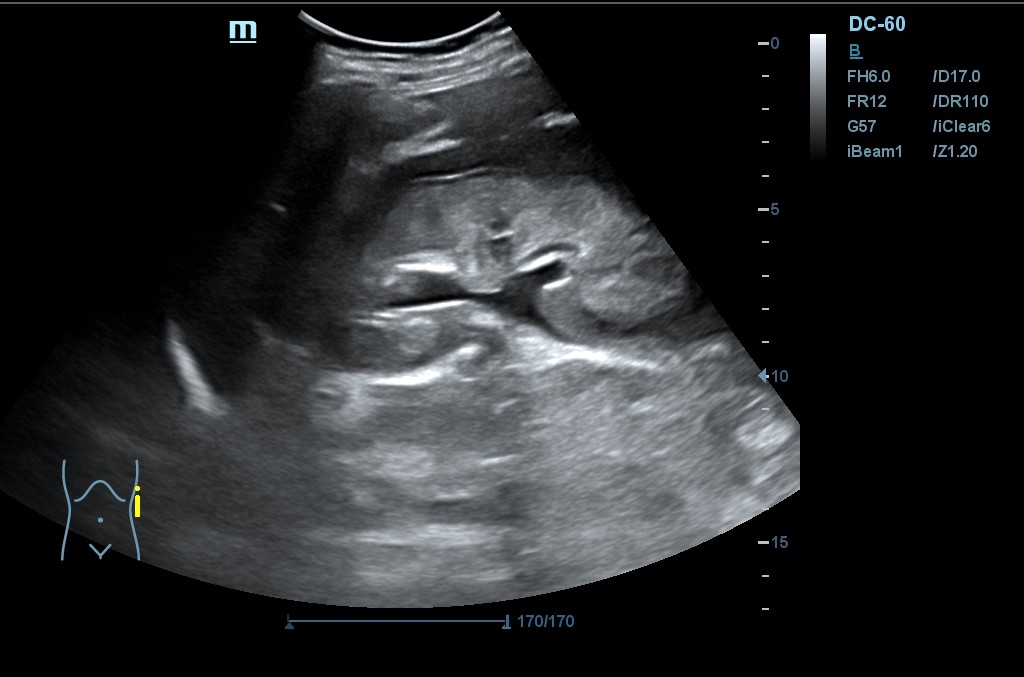

Hallazgo de lo que impresiona de nefromegalia izquierda de aproximadamente 14 cm con hidronefrosis bilateral grado 2.

Se realiza una nueva ecografía en la que se confirma la ascitis y persisten las alteraciones renales.

Tras la segunda ecografía se deriva a la paciente a la Unidad de Diagnóstico Rápido de Medicina Interna donde ingresa para completar estudio. Tras ecografía en la que informan de extenso tejido hipoecoico periaórtico y perirrenal izq. (nefromegalia izq.) con extensión nodular al mesenterio, se establece la sospecha de síndrome linfoproliferativo, así como en un TC posterior y que se confirma como Linfoma No Hodgkin mediante biopsia.